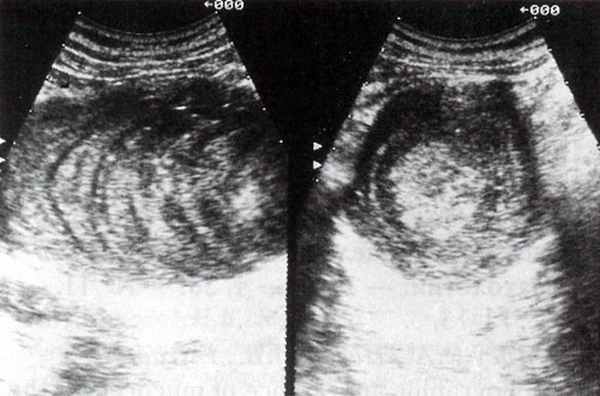

При ультразвуковом исследовании в правой подвздошной области определяется образование Г-образной формы с четкими контурами, размером 12,7 х 6,4 х 5,9 см, подвижное, в начале исследования образование располагалось поперечно, в конце исследования переместилось вверх и расположилось вдоль восходящего отдела толстого кишечника и начальной трети поперечно-ободочной кишки. Структура образования неоднородная за счет правильного чередования зон повышенной и пониженной эхогенности толщиной 2-6 мм. Отчетливо определяются симптомы дорзального усиления звука и латеральные акустические тени (рис. 2). Свободной жидкости в брюшной полости, патологически увеличенных лимфатических узлов не выявлено. Печень, почки - без очаговых изменений. Заключение: кистозное образование брюшной полости.

Рис. 2. Мукоцеле червеобразного отростка. Эхограммы правой подвздошной области в продольной и поперечной плоскостях.